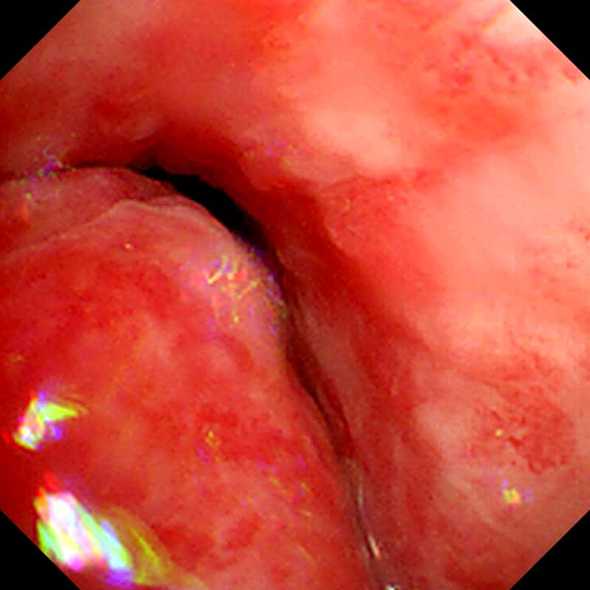

姜云飞和牟海军给患者做支架进行中

支架植入后气管通畅